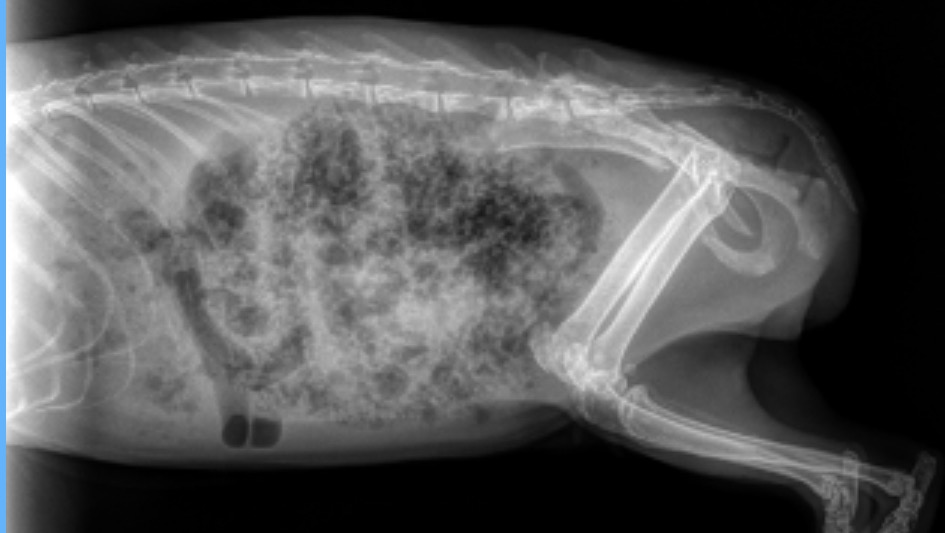

Thora’s story is heartbreaking. She was brought to me after someone admitted that they had intentionally dumped her outside. I called animal control and when the officer picked her up, she was underweight, struggling to walk, and clearly in pain. I brought her to an emergency vet right away, and x-rays showed that her pelvis is fractured in multiple places.

Even with these serious injuries, Thora has shown a strong will to live. She’s eating well, has a big appetite, and can use the bathroom normally. She will need cage rest for several weeks, followed by physical therapy and supportive treatments like laser therapy and acupuncture.

So far, her emergency care has already cost over $1,000. This includes sedation, radiographs, IV fluids, pain medications, and the emergency exam. She will continue to need ongoing veterinary visits and pain control.